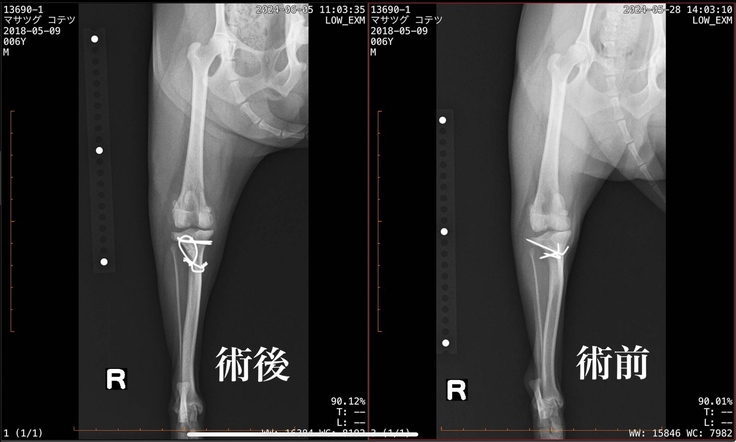

こてつは右膝:グレード4に近い3 左膝:3の診断でした。右膝の症状がこれ以上ひどくならないようにと右膝の手術を行いました。

・前の右膝の手術で挿入したピンが通常は内側に向けて挿入されるべきものが、外側に向けて挿入されているため機能しておらず、触るとクルクルと回ってしまう状態。そのため一度手術した場所も再度手術が必要。

手術は無事に最高しましたが再手術となった右側に関しては、元々入っていたピンのせいで骨が脆くなっている状態でワイヤーも使って固定をしなければなりませんでした。

また役割を果たしていなかったピンが皮下で組織を刺激し、軟組織が過剰に増えている状態でありその組織も切除が必要だったそうです。

(術前後レントゲン)